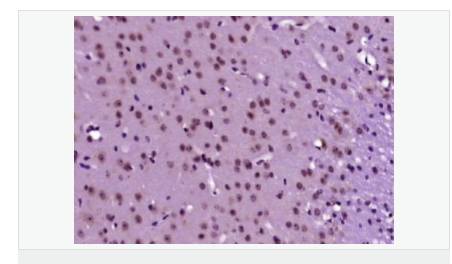

產(chǎn)品應(yīng)用WB=1:500-2000 ELISA=1:5000-10000 IHC-P=1:100-500 IHC-F=1:100-500 ICC=1:100-500 IF=1:100-500 (石蠟切片需做抗原修復(fù))

細(xì)胞定位細(xì)胞核 細(xì)胞漿